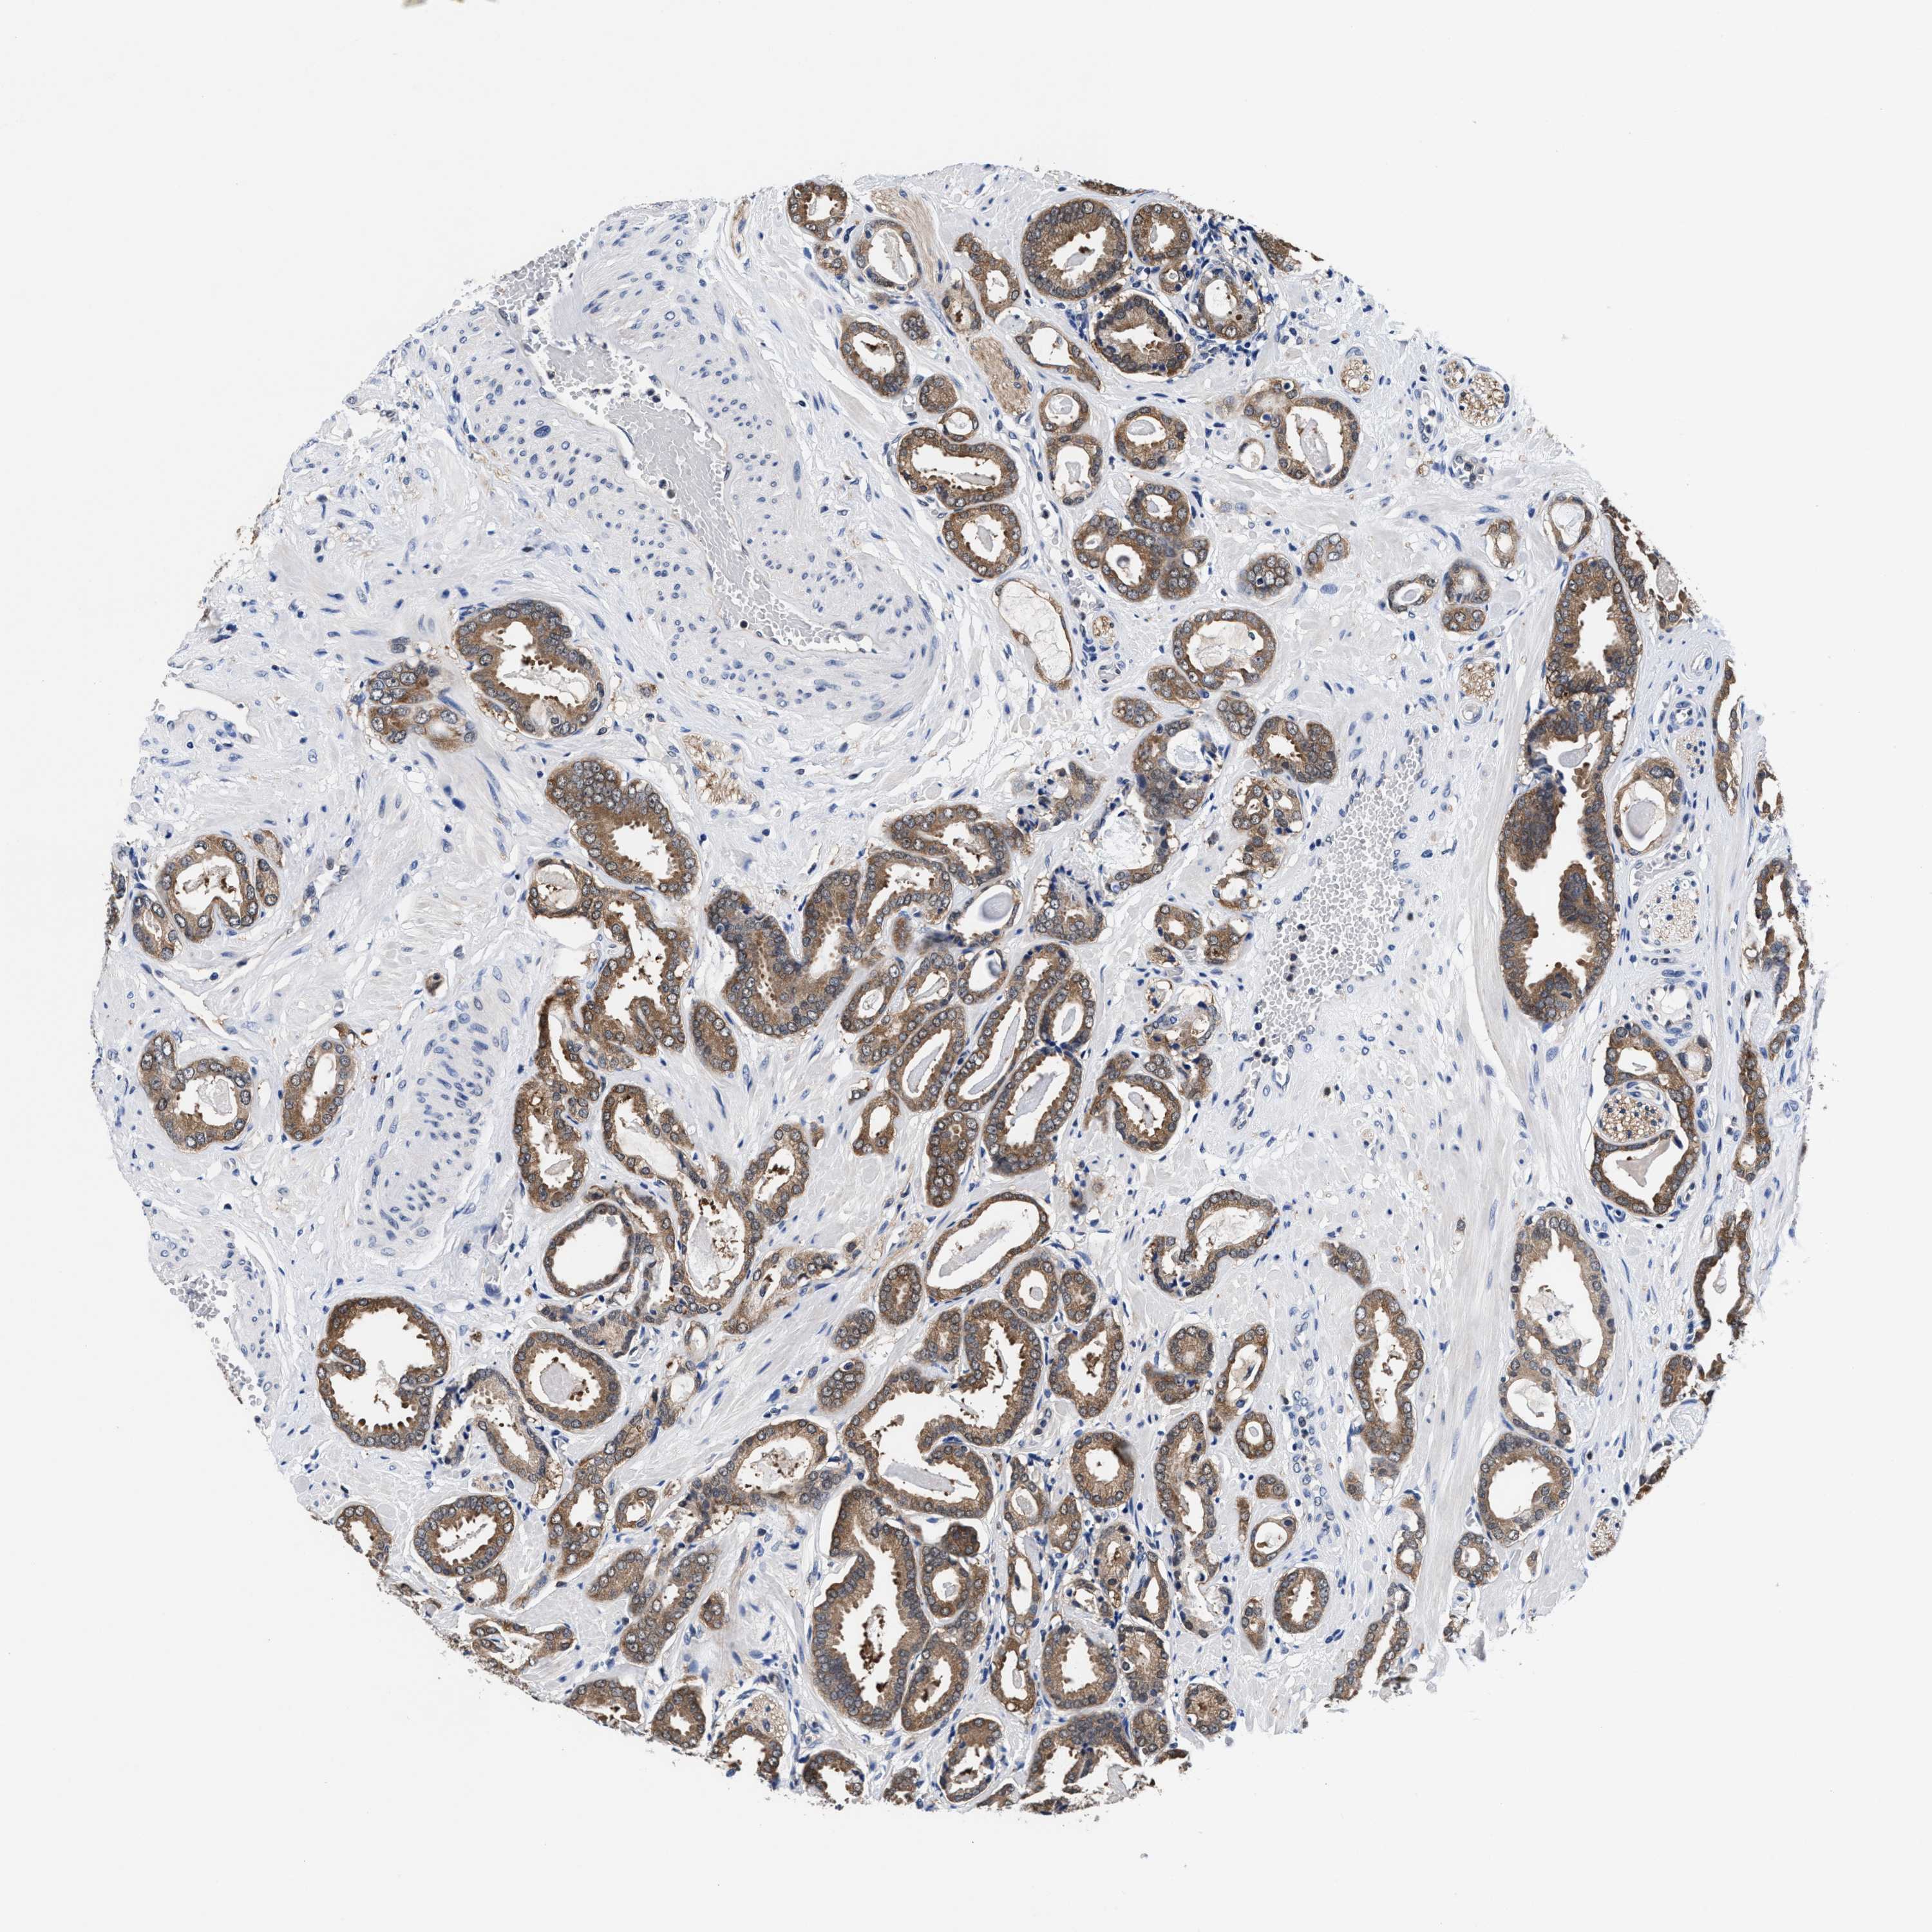

PROSTATE CANCER - Protein expressioni

A mouse-over function shows sample information and annotation data. Click on an image to view it in a full screen mode. Samples can be filtered based on level of antibody staining by selecting one or several of the following categories: high, medium, low and not detected. The assay and annotation is described here.

Note that samples used for immunohistochemistry by the Human Protein Atlas do not correspond to samples in the TCGA dataset.

Antibody stainingi

Antibody staining in the annotated cell types in the current human tissue is reported as not detected, low, medium, or high, based on conventional immunohistochemistry profiling in selected tissues. This score is based on the combination of the staining intensity and fraction of stained cells.

Each image is clickable and will lead to virtual microscopy that enables deeper exploration of all samples and also displays staining intensity scores, fraction scores and subcellular localization as well as patient and tissue information for each sample.

Adenocarcinoma, High grade

Adenocarcinoma, Low grade